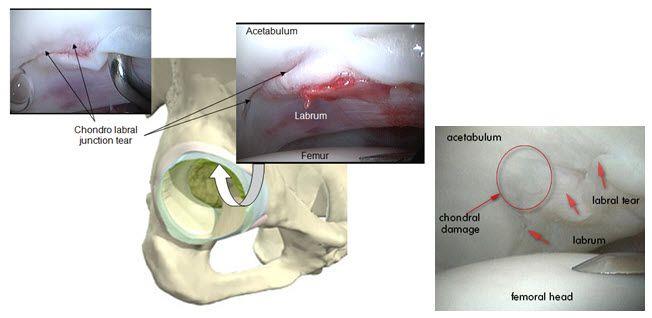

דוגמאות לקרעים בלברום והטיפול בהם:

לפתח הגרמי של האצטבולום, צמודה טבעת סחוסית גמישה שנקראת הלברום האצטבולארי. טבעת זו מעמיקה את המכתש, מייצבת את ראש הירך בתוכו ואוטמת את מעבר הנוזל בתוך הפרק בצורה שמייעלת את פיזור הכוחות שמופעלים על הסחוסים.

במצבים בהם מביאים את הירך לטווחים קיצוניים, אנו עלולים לכתוש את הלברום בין שני צדי המפרק כאשר צוואר הירך צובט את הלברום שיושב על הגבול של האצטבולום ובכך גורם לנזק שעלול לפגום ביכולת שלו לייצב ולאטום.

בנוסף, הלברום הוא המשכי לציפוי הסחוסי של האצטבולום, כך שפגיעה בו עלולה לגרום לנזק בסחוס הסמוך לבסיסו.

תסמונת התפס הפמורו אצטבולארית

שינויים במבנה האנטומי של מפרק הירך יכולים להביא ל"התנגשות" מוקדמת בין שני הצדדים וכך לגרום נזק ללברום ולסחוס. לקונפליקט בין ראש הפמור האצטבולום אנחנו קוראים "תפס" או "צביטה" (ובאנגלית, impingement).